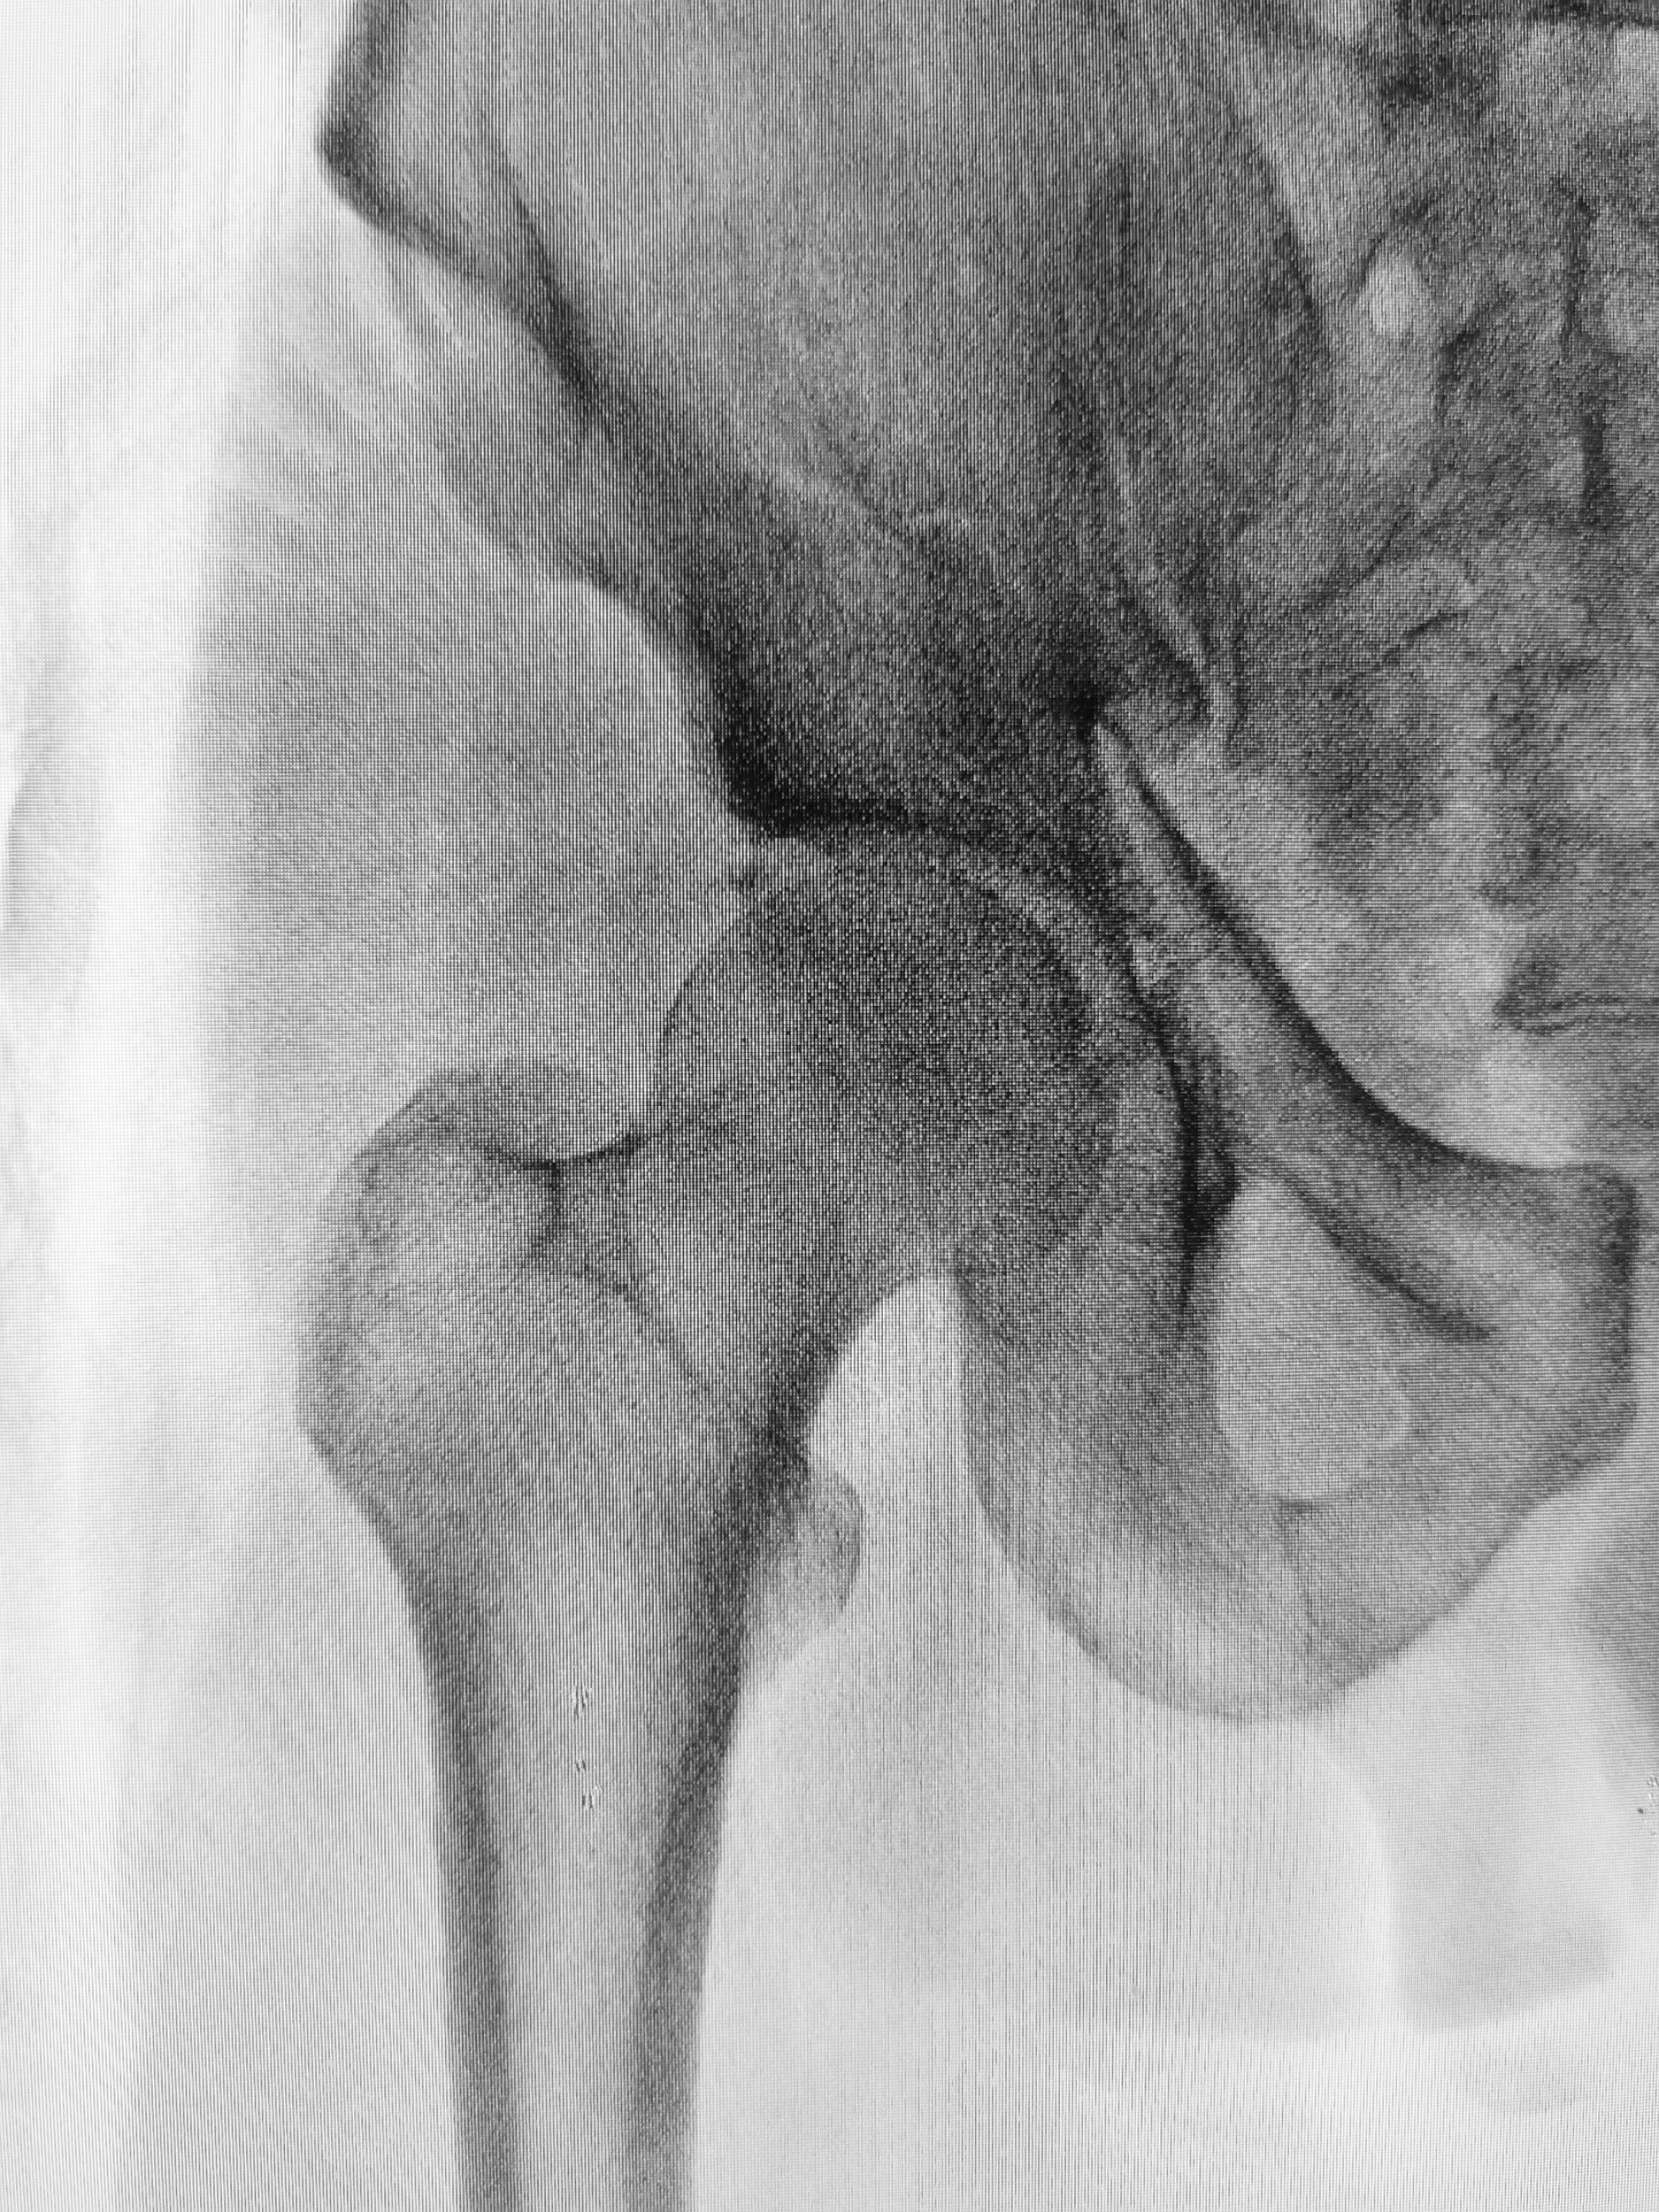

NOF